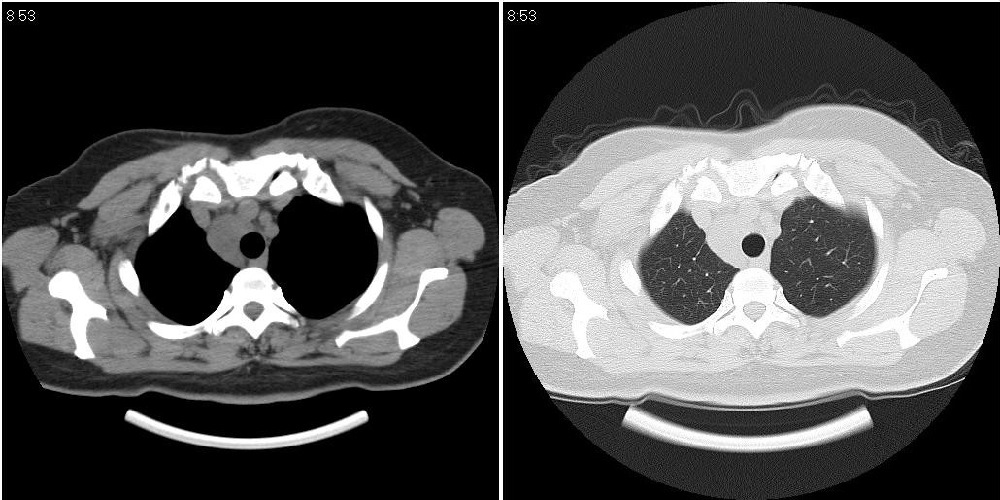

标题: CT24795:女性,47岁,右下腿静脉静脉曲张手术前体检,发现 [打印本页]

标题: CT24795:女性,47岁,右下腿静脉静脉曲张手术前体检,发现

囊性无明显占位效应:1淋巴管囊肿2畸胎瘤(其上部见小钙化)3前肠囊肿

右上纵隔囊性占位性病变;考虑淋巴管囊肿,不排除支气管囊肿。

支气管囊肿、囊性畸胎瘤、肠源性囊肿均有可能。

右上纵隔囊性占位性病变;考虑淋巴管囊肿,不排除支气管囊肿。 建议增强。

考虑淋巴管囊肿,不排除前肠囊肿。